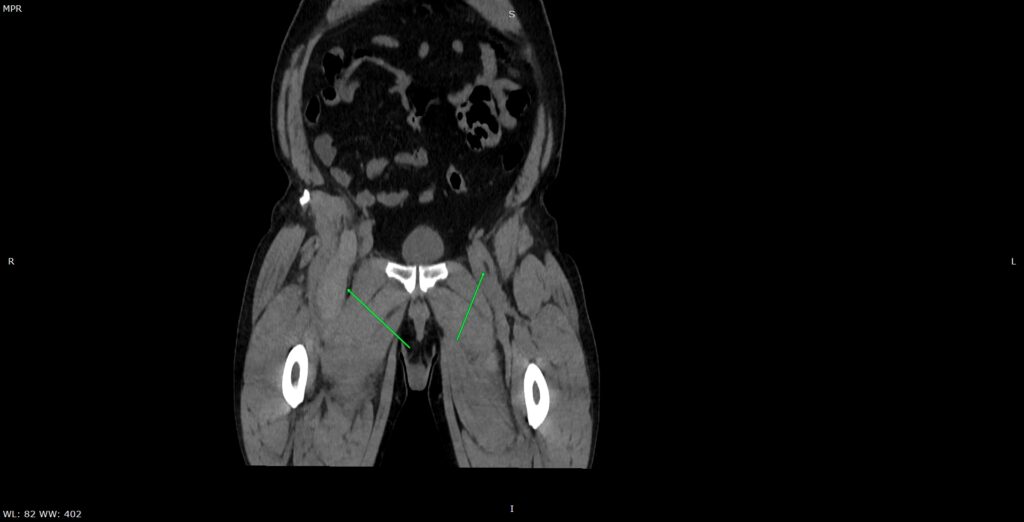

Figura 3: reconstrucție oblic coronală din achiziție CT fără contrast posttraumatic imediat

Discuţie caz nr 134: Pe imaginile achiziționate fără substanță de contrast se remarcă creștere marcată de volum a muschiului ilio-psoas drept în două treimi distale cu evidențierea unei plaje întinse cu densități sangvine ce sugerează prezența unui hematom posttraumatic; nu se evidențiază traiecte de fractură. Achiziția de control după 22 de luni evidențiază reducerea grosimii corpului muscular ilio-psoas drept cu încărcare grăsoasă care, pe alocuri, afectează aproape complet corpul muscular.